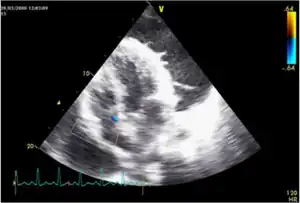

Tuberculous pericarditis

Tuberculous pericarditis is a form of pericarditis.